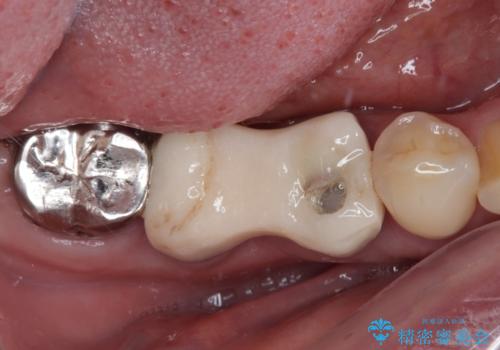

- むし歯を放置したままで、インプラント治療を希望して来院された患者様です。

左右ともにインプラントが必要な状態でした。

左下小臼歯は根管治療で対応する予定でしたが、診断のために歯肉を開いたところ頬側に垂直破折が認められたため、抜歯即時埋入インプラントによる補綴治療を選択することとしました。